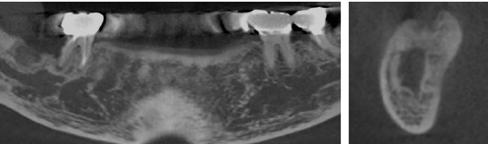

Vizsgálatok

A pótlásra szoruló fogat, vagy fogakat minden esetben legalább egy évvel a fogpótlást megelőzően eltávolítottuk. Ezen esetek egyikében sem végeztünk alveolus vagy állcsontgerinc prezervációt az eltávolítás során, illetve minden páciens jó szájhigiéniával rendelkezett. Egy kivételével minden páciensnél radiológiai analízist végeztünk CBCT-vel, amelyet

digitális implantátumtervezés követett (SICAT és Sidexis, mindkettő Dentsply Sirona; 1. ábra).